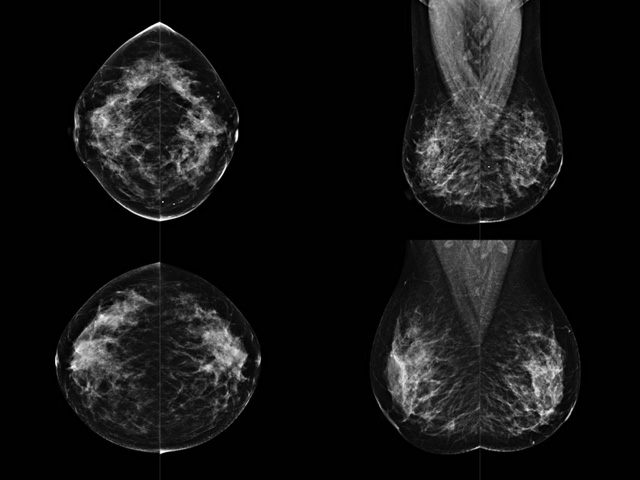

乳腺DR檢查的作用跟有什么細節需要注意事項

乳房檢查時候要注意一些細節,需要更深入的了解這樣才能使檢查更準確。乳腺DR是乳腺癌的篩查診斷工具設備。是乳房方面檢查的重要影像方法。它可以臨床檢查出早期的乳腺癌。可以判斷良性惡性。因為它可以檢查出早期的病變。對良性惡性檢查的準確率達到90%以上。發病高峰年齡為45歲到54歲。50歲檢查出來乳腺癌病患,可以讓死亡率下降3成。所以30-40歲女性每年做一次乳腺DR檢查。40歲以上就一年兩次。如果家族史有乳腺癌的30歲以下也需要做檢查。清晰顯示乳腺各層組織嚴重的乳腺增生,乳腺炎,乳腺外傷也建議1年檢查一次。極大提高了早期乳腺癌的敏感度和診斷率。

大角度、高質量的乳腺檢查,可以讓女性帶來身體健康安全。為醫生提供了高清影像數據。乳腺檢查時候各個部位影像顯示出來。白色乳腺導管跟纖維結締組織。模糊的是脂肪。病變一般是不透明的白色。有需要放大來檢查。乳腺DR沒有重疊偽影。輻射劑量更少。因為乳腺癌發病每年都有所提高,對女性都造成了嚴重的身體健康危害。早做檢查早治療是不可忽視的舉措。可以大大的降低死亡率。保證身體健康。一般檢查避開經期,來完7天左右是最佳的檢查時間。絕經的女性就沒有要求。孕婦不參加乳腺DR檢查, 6個月內準備妊娠的婦女也不宜行此檢查。